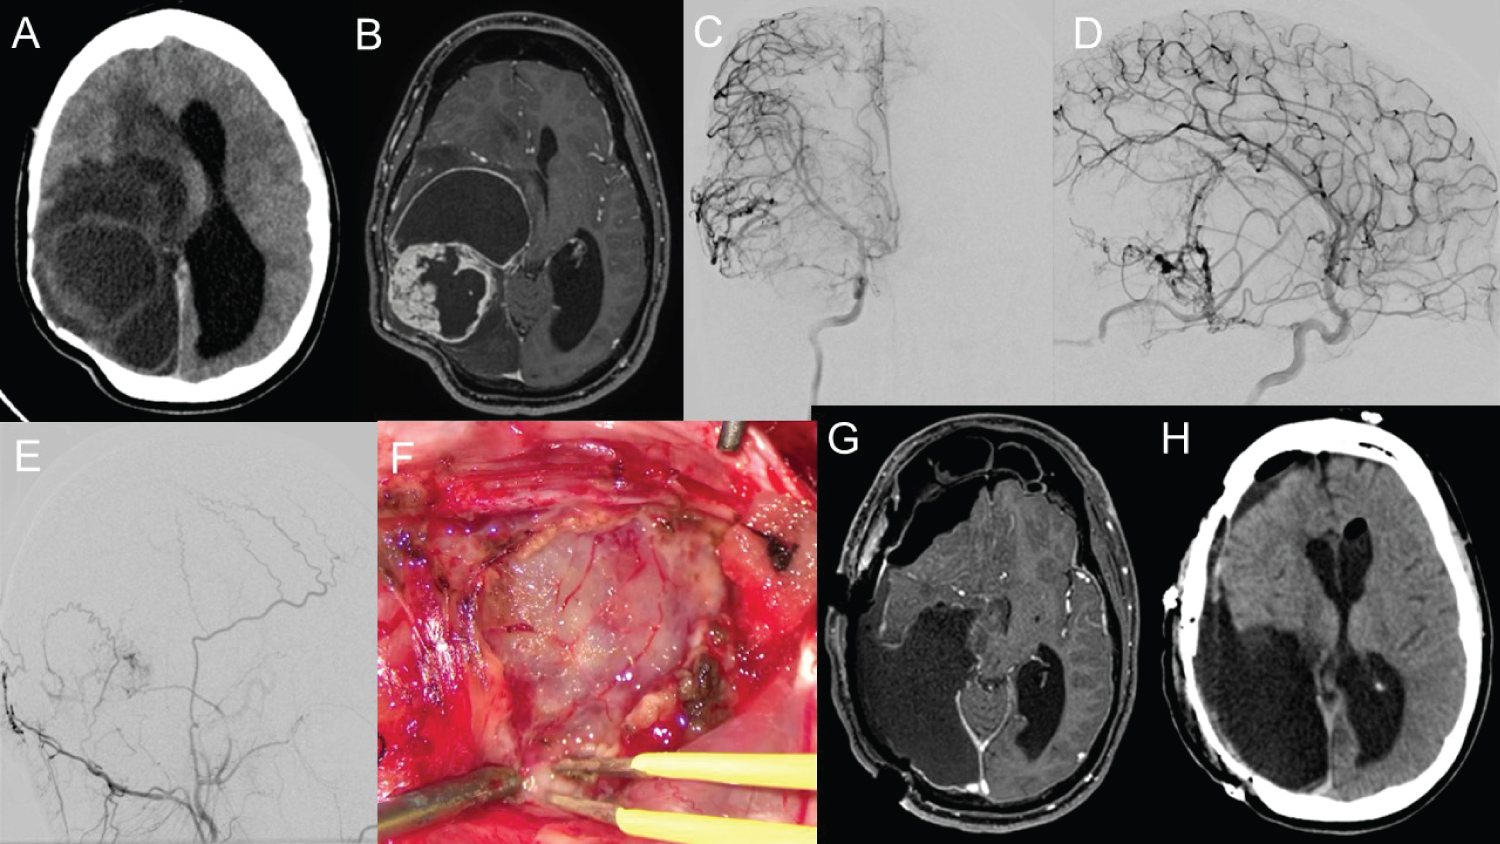

A 38-year-old man presented with ataxia, vertigo, and vomiting in our department. His head CT and brain MRI revealed multiple cystic solid tumors in the cerebellar region (Figure 3A and Figure 3B). An angiogram of the right vertebral artery revealed no apparent feeding arteries (Figure 3C). Surgical GTR was performed (Figure 3D), and a histopathological examination revealed a PA with varying proportions of compacted bipolar cells and loose microcystic areas. We observed numerous eosinophilic granular bodies (Figure 3E) and rare mitotic figures. The tumor cells were positive for GFAP (Figure 3F) and negative for CD34, p53, and IDH-1. ATRX was absent in the tumor cell nuclei. The Ki-67 index was approximately 1%, and the mRS score was comparable before and after the operation. No recurrence was observed for 10 years after tumor removal.

Figure 3: Images and pathological findings of Case 2.

Head computed tomography (CT) (A) and brain magnetic resonance imaging (MRI) (B) in Case 2 revealed multiple cystic solid tumors in the cerebellar region. An angiogram of the right vertebral artery revealed no apparent feeding arteries (C). Surgical gross total resection was confirmed in postoperative MRI (D), and a histopathological examination revealed a pilocytic astrocytoma with varying proportions of compacted bipolar cells and loose microcystic areas. Numerous eosinophilic granular bodies (E) and rare mitotic figures are present. The tumor cells are positive for GFAP (F). View Figure 3